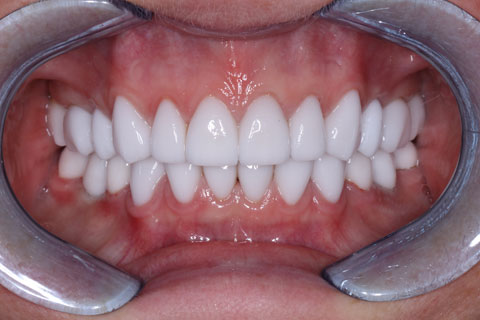

Проведена ортопедическая реабилитация.

Фронтальная группа зубов верхней и нижней челюстей – установлены виниры из литий дисиликата.

Жевательная группа – восстановлена коронками из диоксида циркония, в том числе 3.6, 4.6 – коронки на имплантатах.